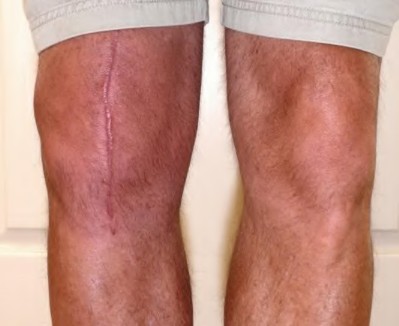

Question 4:

A 22-year-old female soccer player undergoes primary anterior cruciate ligament (ACL) reconstruction using a bone-patellar tendon-bone autograft. Postoperatively, she experiences loss of terminal extension and anterior knee pain. An MRI indicates graft impingement against the intercondylar roof. Which of the following technical errors during tunnel preparation is the most common cause of this specific impingement pattern?

Correct Answer: Tibial tunnel placed too anteriorly

Explanation:

Placing the tibial tunnel too anteriorly is the most common cause of intercondylar roof impingement. The tibial tunnel should be placed posterior to the intersection of Blumensaat's line and the tibial plateau when the knee is in full extension. If placed anterior to this line, the graft will impinge on the notch roof during terminal extension, leading to a loss of extension and potential graft failure.